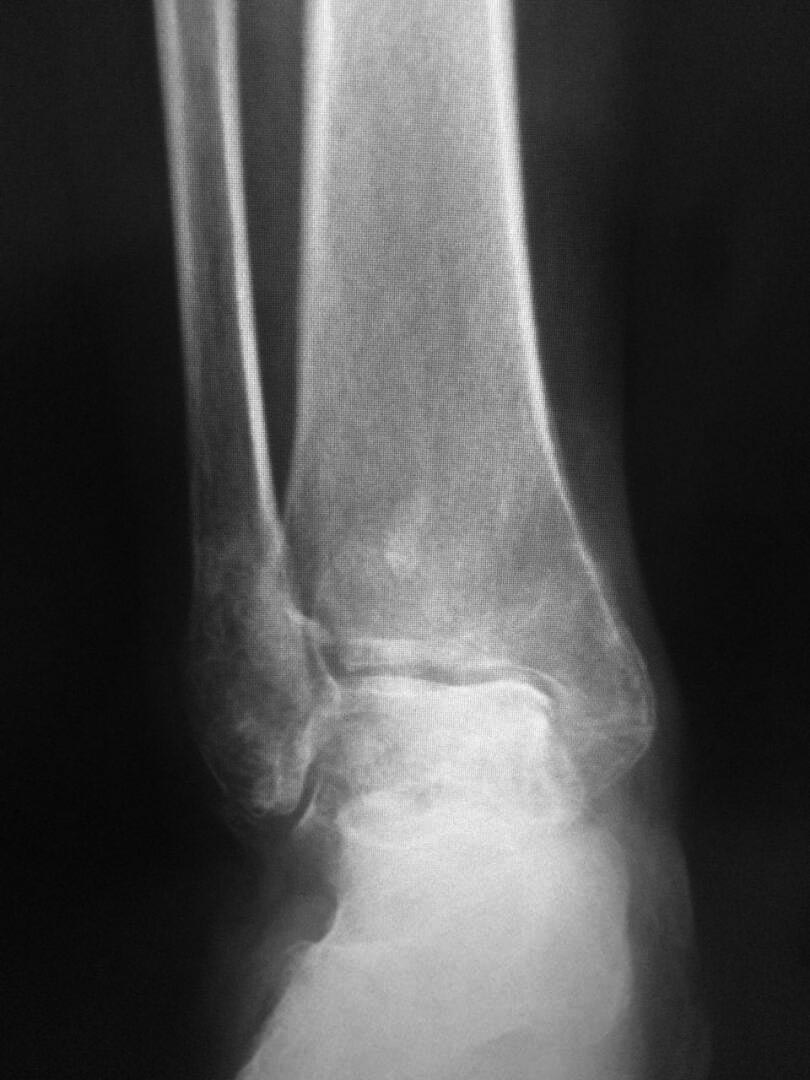

Пациентка 60л. 3 месяц назад получила травму г/стоп сустава: перелом обеих лодыжек, заднего края с подвывыхом стопы. Нигде не лечилась. Мне пригласили на консультацию в другую обл.. Все идет к артродезу. У нее еще сахарный диабет. Лет 10 назад я в Екатеринбурге видел как доктор Челноков сделал артродез г/стоп сустава закрытым способом с PFN ChM .Вот я тоже думаю об этом, но технику подзабыл, уважаемые коллеги может кто нибудь поможеть мне, или может сам Александр Николаевич поможет я очень надеюч на яваше помощь. С уважением Абдурашид

Со снимками понятнее. С таким подвывихом не походишь. Я бы попытался выполнить репозицию и остеосинтез наружной лодыжки. А если не получится, можно сразу же ее резецировать и через открывшийся доступ к суставу удалить хрящевое покрытие, сопоставить суставные поверхности и произвести артродез винтами. Доступ к лодыжке небольшой, через него можно ввести пару винтов. А еще 2 через проколы мягких тканей на внутренней поверхности. Это достаточно малоинвазивный способ с сохранением подтаранного сустава. И дешевле намного.